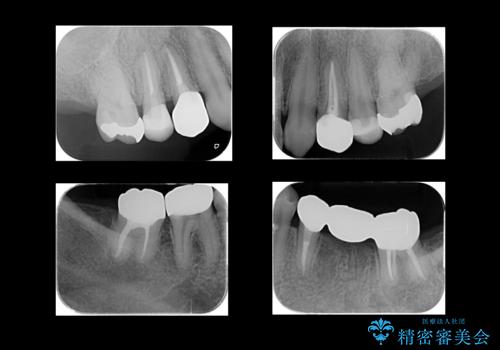

全体的な虫歯治療

- 左下の虫歯を主訴に来院。

全体的に虫歯もあったため治療を行いました。

- 187万円(税込)(内訳:歯周外科処置 右上および左下臼歯部 15万円×2 右下67、左下⑤6⑦、右上4、左上4 ジルコニアクラウン 11万円×7 仮歯1万円×7 左下7再根管治療 15万円×1 左上4右上4左下5再根管治療11万円×3 ファイバーコア×4)費用は治療当時の料金となります